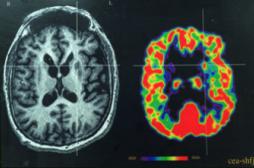

neuroimagerie